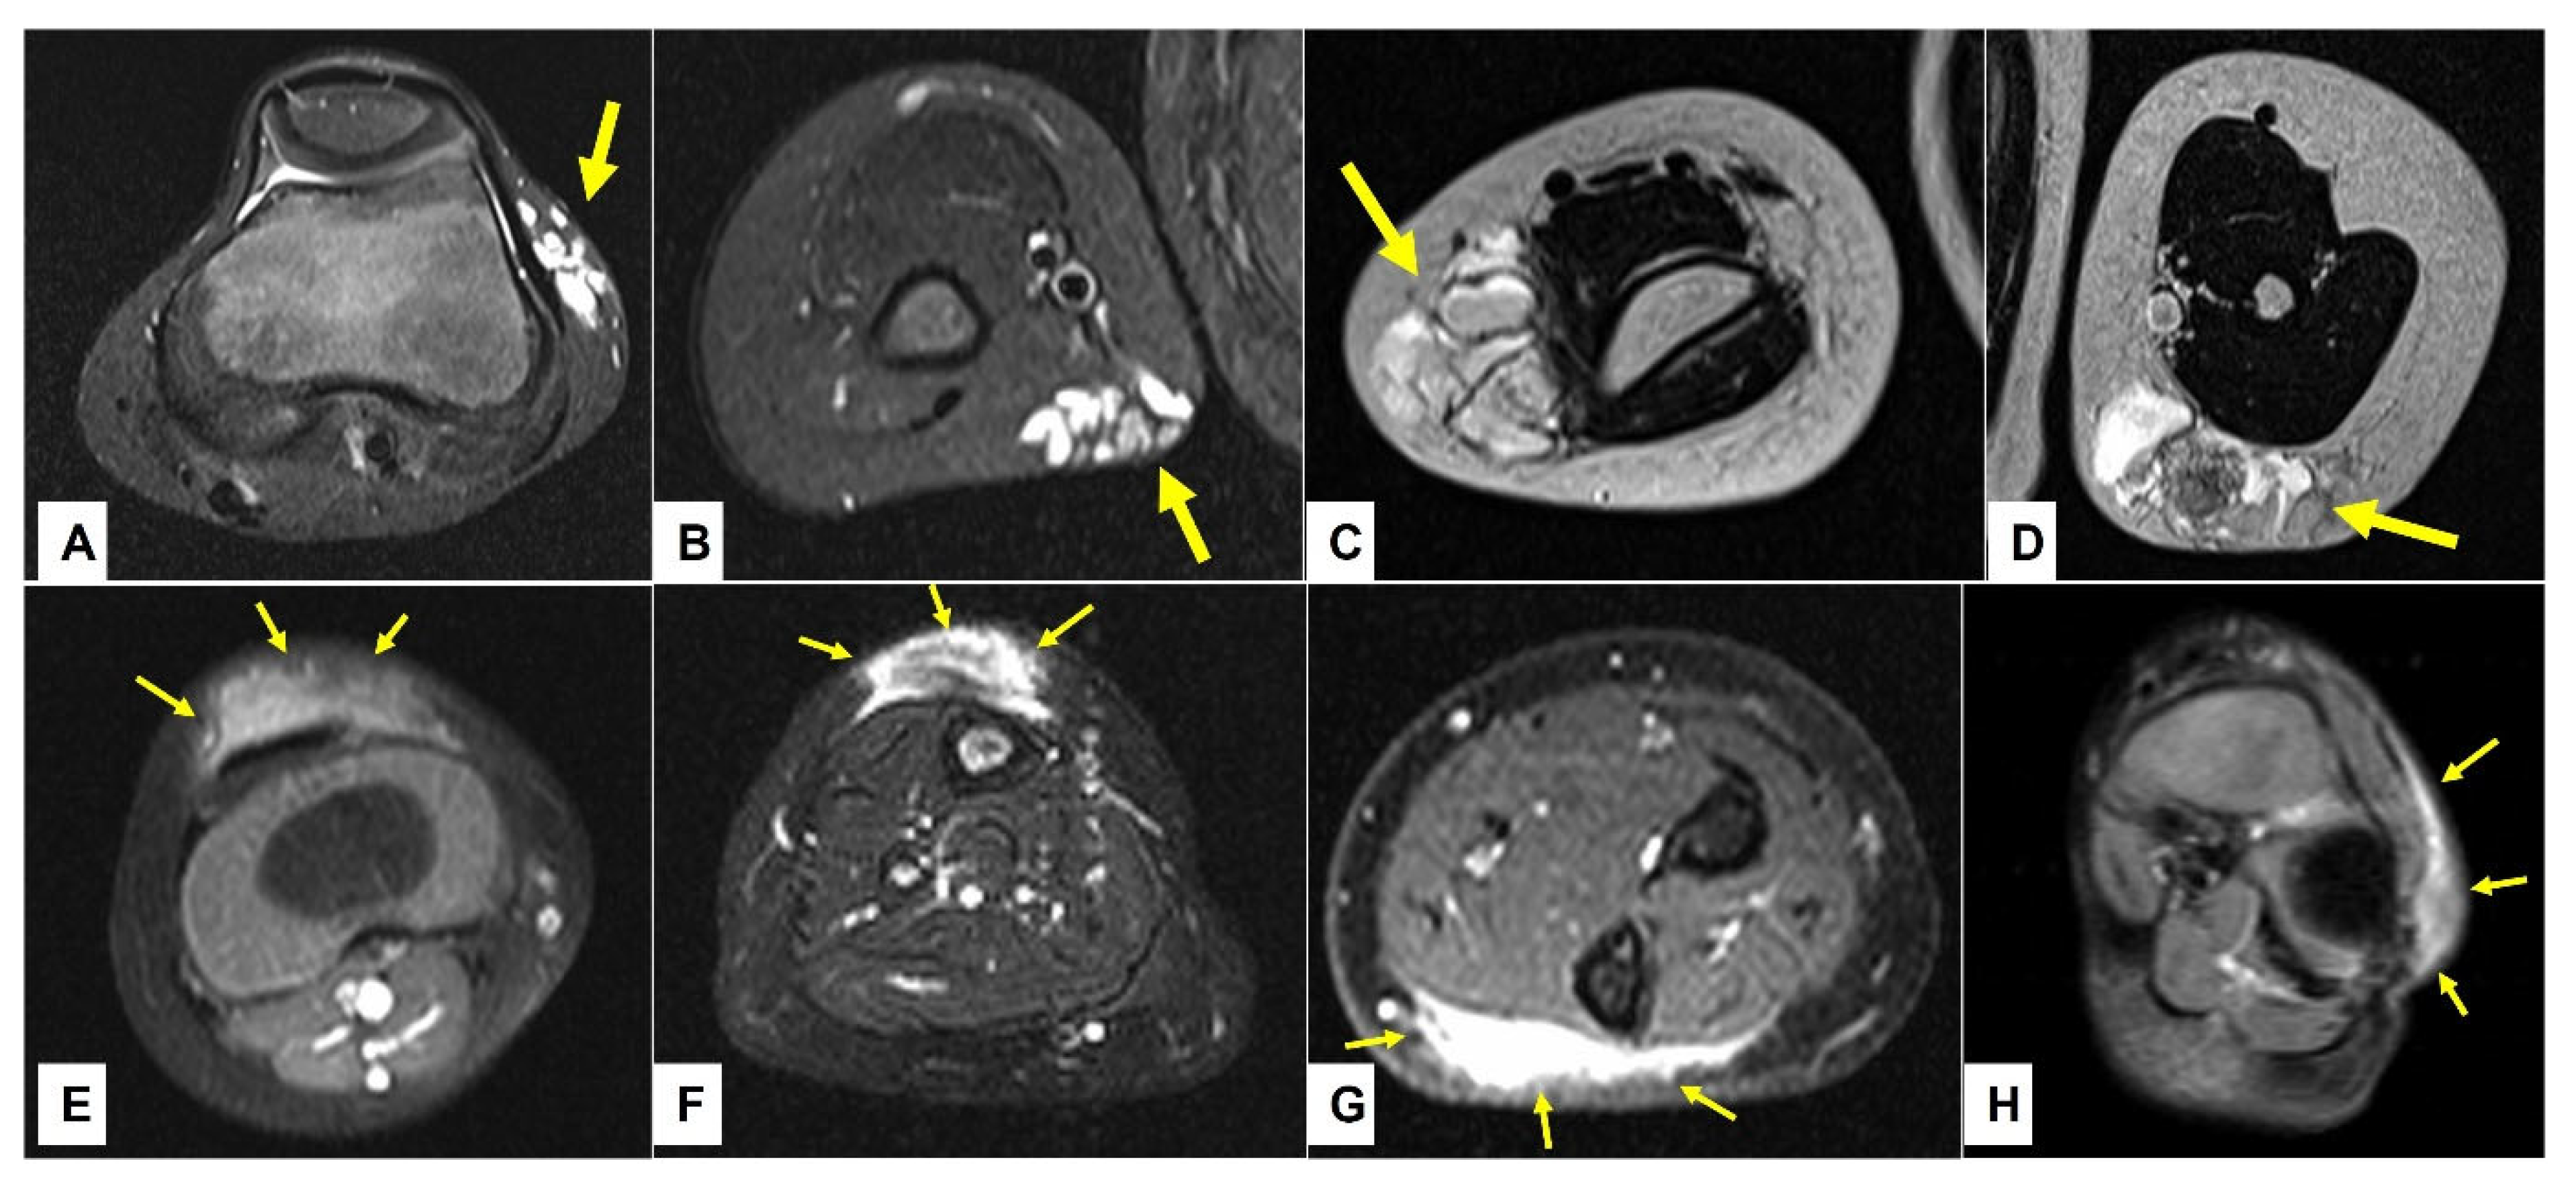

Figure 7.

This composite figure illustrates a subcutaneous lump on the right lower leg of a 12-month-old girl (A)—(arrows). X-ray at presentation showed a cloudy pretibial soft-tissue lesion with no osseous deformities (B)—(arrows). Ultrasound imaging of the lesion was unspecific but showed some small cystic areas in the deep dermis (E)—(arrows). MR imaging at the age of 13 months showed a strict epifascial tubulo-cystic lesion in the subcutaneous tissue in the anterolateral area without contrast enhancement (C,D,F,G)—(arrows).